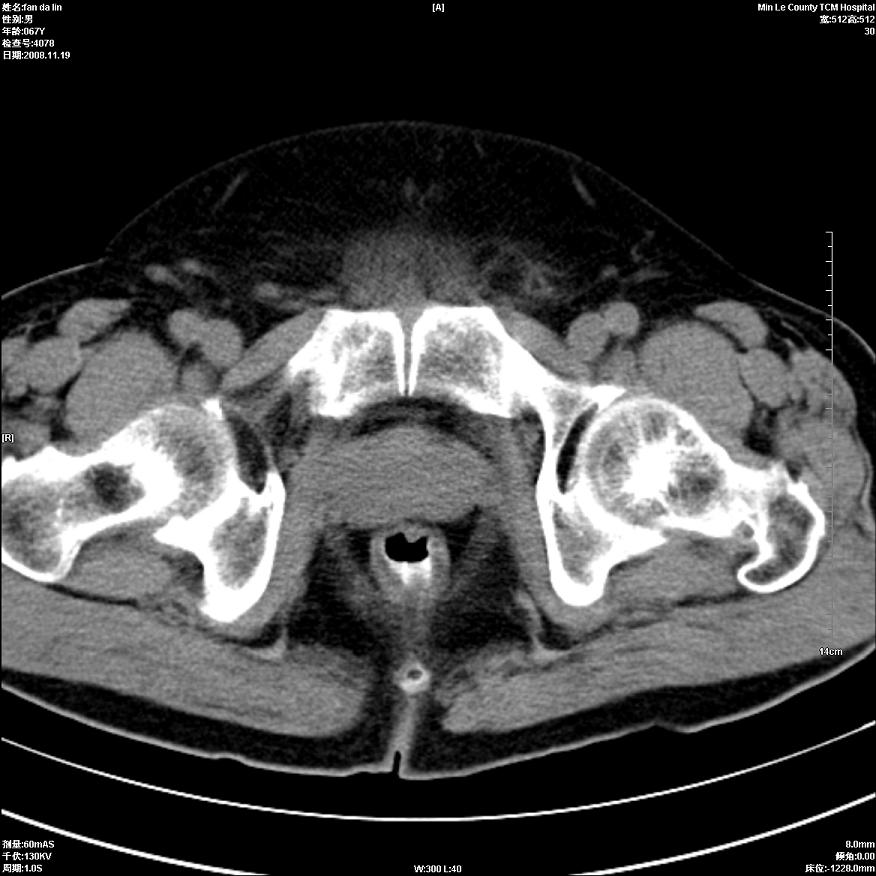

标题: CT16698:M67Y,看看直肠下端是不是病变 [打印本页]

标题: CT16698:M67Y,看看直肠下端是不是病变

粘膜皱壁,不除外内痔

直肠及乙状结肠管壁均增厚,考虑炎症.

直乙交界处肠壁不规则增厚,还是做个肠镜吧

只是肠壁局限性增厚,但难说明问题。